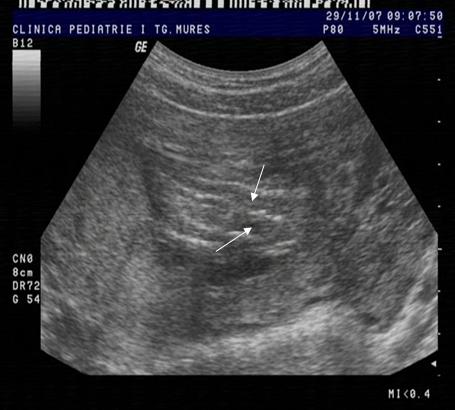

Fig. nr.108. Sarcina 7 saptamani la ecografia abdominala.